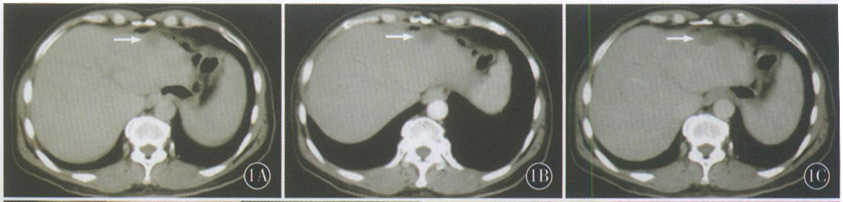

本例患者术中所见分析原因考虑为局部植入用缓释氟尿嘧啶剂量较大,药物被局部组织包绕后长时间代谢不全,从而导致组织坏死,并伴有肉芽组织增生、纤维组织增生包绕,形成肉芽肿性炎性肿块,术后得到病理证实(图2,3)。

图2术中腹腔镜所见的病灶处,右上角小图为病灶处取出的内容物;图3术后病理提示肉芽组织包绕的无结构物及黏冻样组织为坏死组织(箭头) HE×400